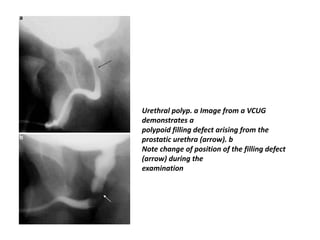

Urethral polyp. a Image from a VCUG

demonstrates a

polypoid filling defect arising from the

prostatic urethra (arrow). b

Note change of position of the filling defect

(arrow) during the

examination

Congenital urethral polyps •Congenital urethral polyps are benign and arise from the prostatic urethra near the verumontanum. • Because they have a stalk, these polyps are mobile and can move proximally into the bladder or distally into the bulbous urethra. • They can be a cause of urethral obstruction or bleeding. • VCUG is diagnostic and demonstrates a mobile filling defect in the bladder neck or below the verumontanum . • Endoscopic resection is the treatment of choice

• 64.

Urethral polyp. aImage from a VCUG demonstrates a polypoid filling defect arising from the prostatic urethra (arrow). b Note change of position of the filling defect (arrow) during the examination